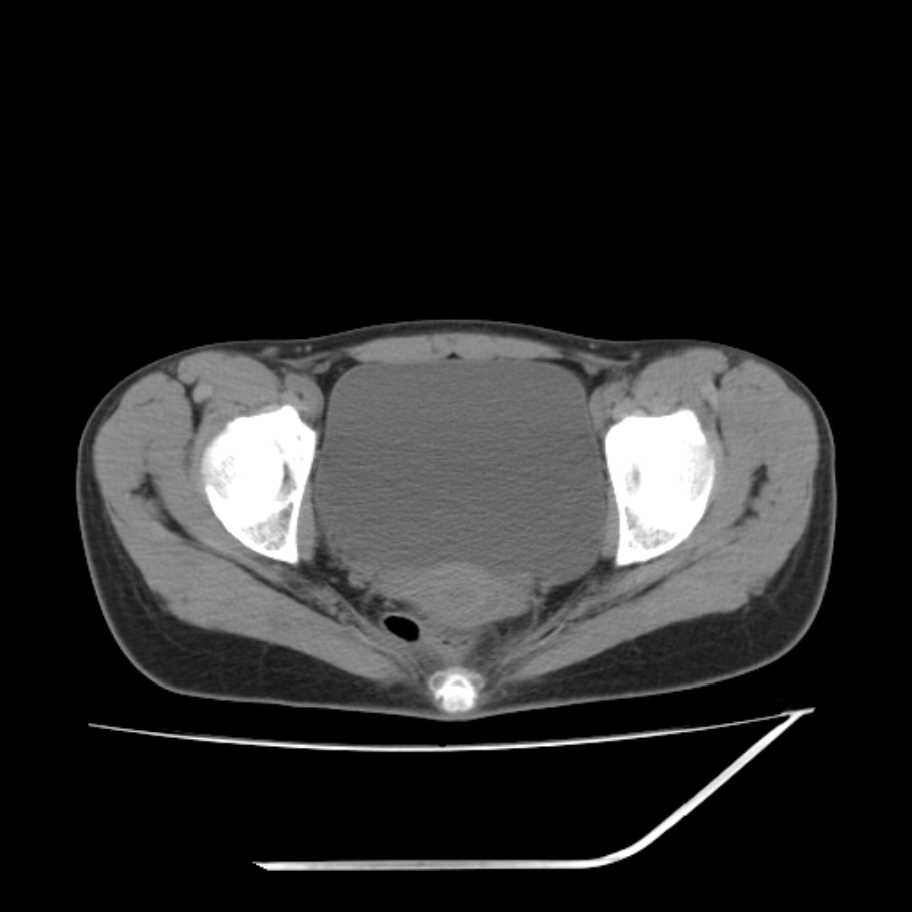

女,25岁。偶尔有右下腹不适感,余无明显异常。(结婚半年),囊壁较厚,是卵巢囊肿吗?

其上一层面见两枚小气泡影,考虑为肠管影可能,不完全除外囊肿

右侧卵巢区椭圆形囊性肿物,内壁光滑 无分隔。直肠子宫间隙内有少量积液征象。结合临床考虑卵巢巧克力囊肿,还要问问有没有痛经,本例ct怎么没有灌肠?要是灌肠或前一前口服造影剂,起码可以和肠管区别开

b超示:囊实性占位,畸胎瘤?临床有痛经。

考虑右侧卵巢囊性占位性病变(巧克力囊肿?),盆腔积液有不排除宫外孕可能,请结合临床和b超。

右侧卵巢囊伴盆腔少量积液。